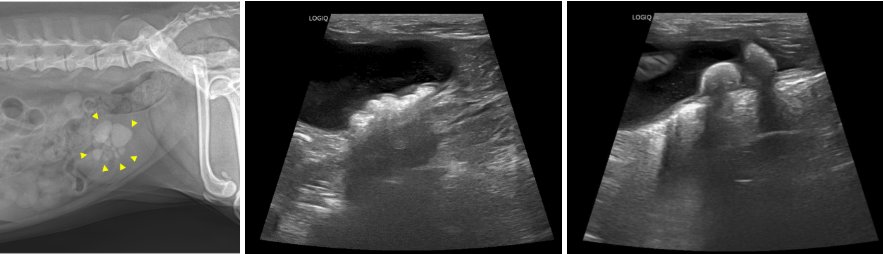

01 영상 검사

보호자님과 상담 후 x-ray와 초음파 검사를 진행했습니다. 그결과 방광 내 다수의 결석이 재차 확인되었습니다.

강아지 결석 X-Ray(1), 강아지 초음파 (2, 3) / 출처: 에스동물메디컬센터 양산점